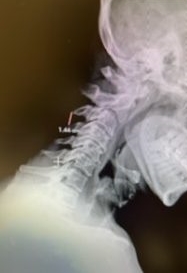

(2b) Lateral Flexion cervical x-rays extension image demonstrating 8mm of splaying of the C34 interspinous distance.

The fluid was possibly consistent with CSF versus chronic hematoma. The patient was also noted to have a high signal within the interspinous space of C3-C4. This high signal was consistent with a ruptured C3-4 interspinous ligament. Cervical flexion-extension x-rays demonstrated 6 mm of widening of the C3-4 interspinous space on flexion x-ray consistent with cervical instability (Fig. 2a and 2b).